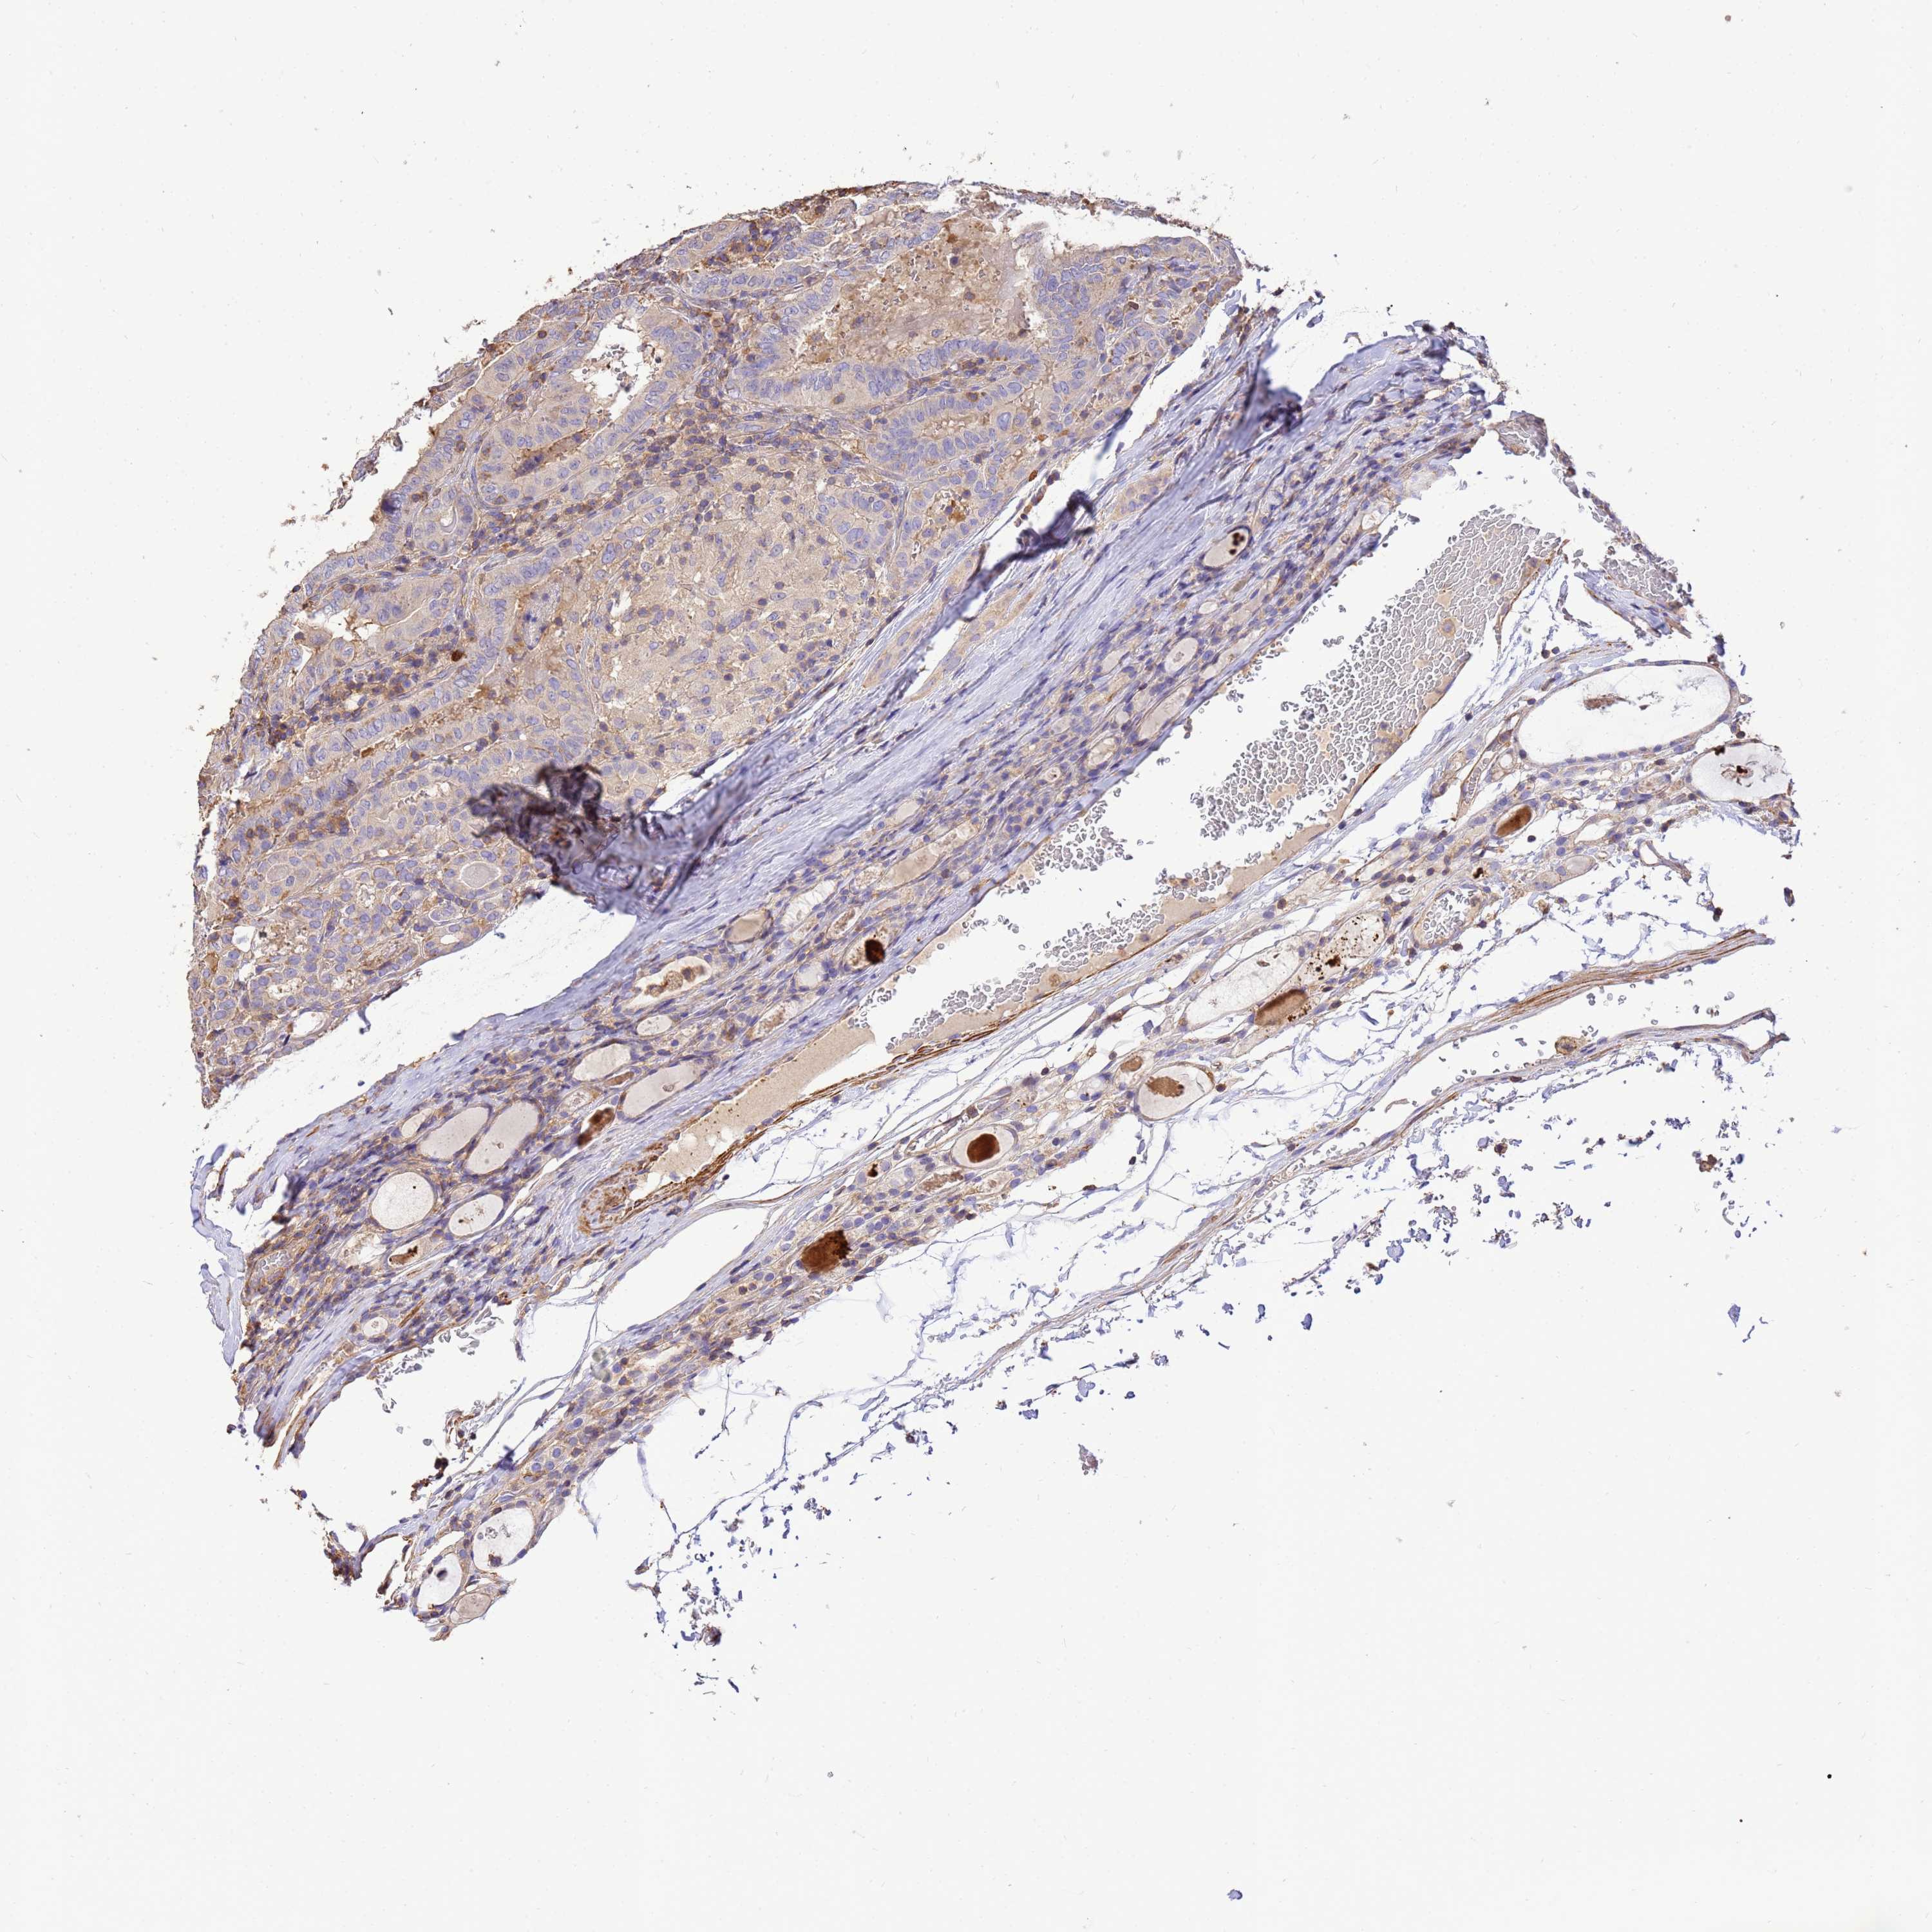

THYROID CANCER - Protein expressioni

A mouse-over function shows sample information and annotation data. Click on an image to view it in a full screen mode. Samples can be filtered based on level of antibody staining by selecting one or several of the following categories: high, medium, low and not detected. The assay and annotation is described here.

Note that samples used for immunohistochemistry by the Human Protein Atlas do not correspond to samples in the TCGA dataset.

Antibody stainingi

Antibody staining in the annotated cell types in the current human tissue is reported as not detected, low, medium, or high, based on conventional immunohistochemistry profiling in selected tissues. This score is based on the combination of the staining intensity and fraction of stained cells.

Each image is clickable and will lead to virtual microscopy that enables deeper exploration of all samples and also displays staining intensity scores, fraction scores and subcellular localization as well as patient and tissue information for each sample.

Antibody HPA046186

Staining

High

Medium

Low

Not detected

Intensity

Strong

Moderate

Weak

Negative

Quantity

>75%

75%-25%

<25%

None

Location

Nuclear

Cytoplasmic/membranous

Cytoplasmic/membranous,nuclear

Papillary adenocarcinoma, NOS

Follicular adenoma carcinoma, NOS